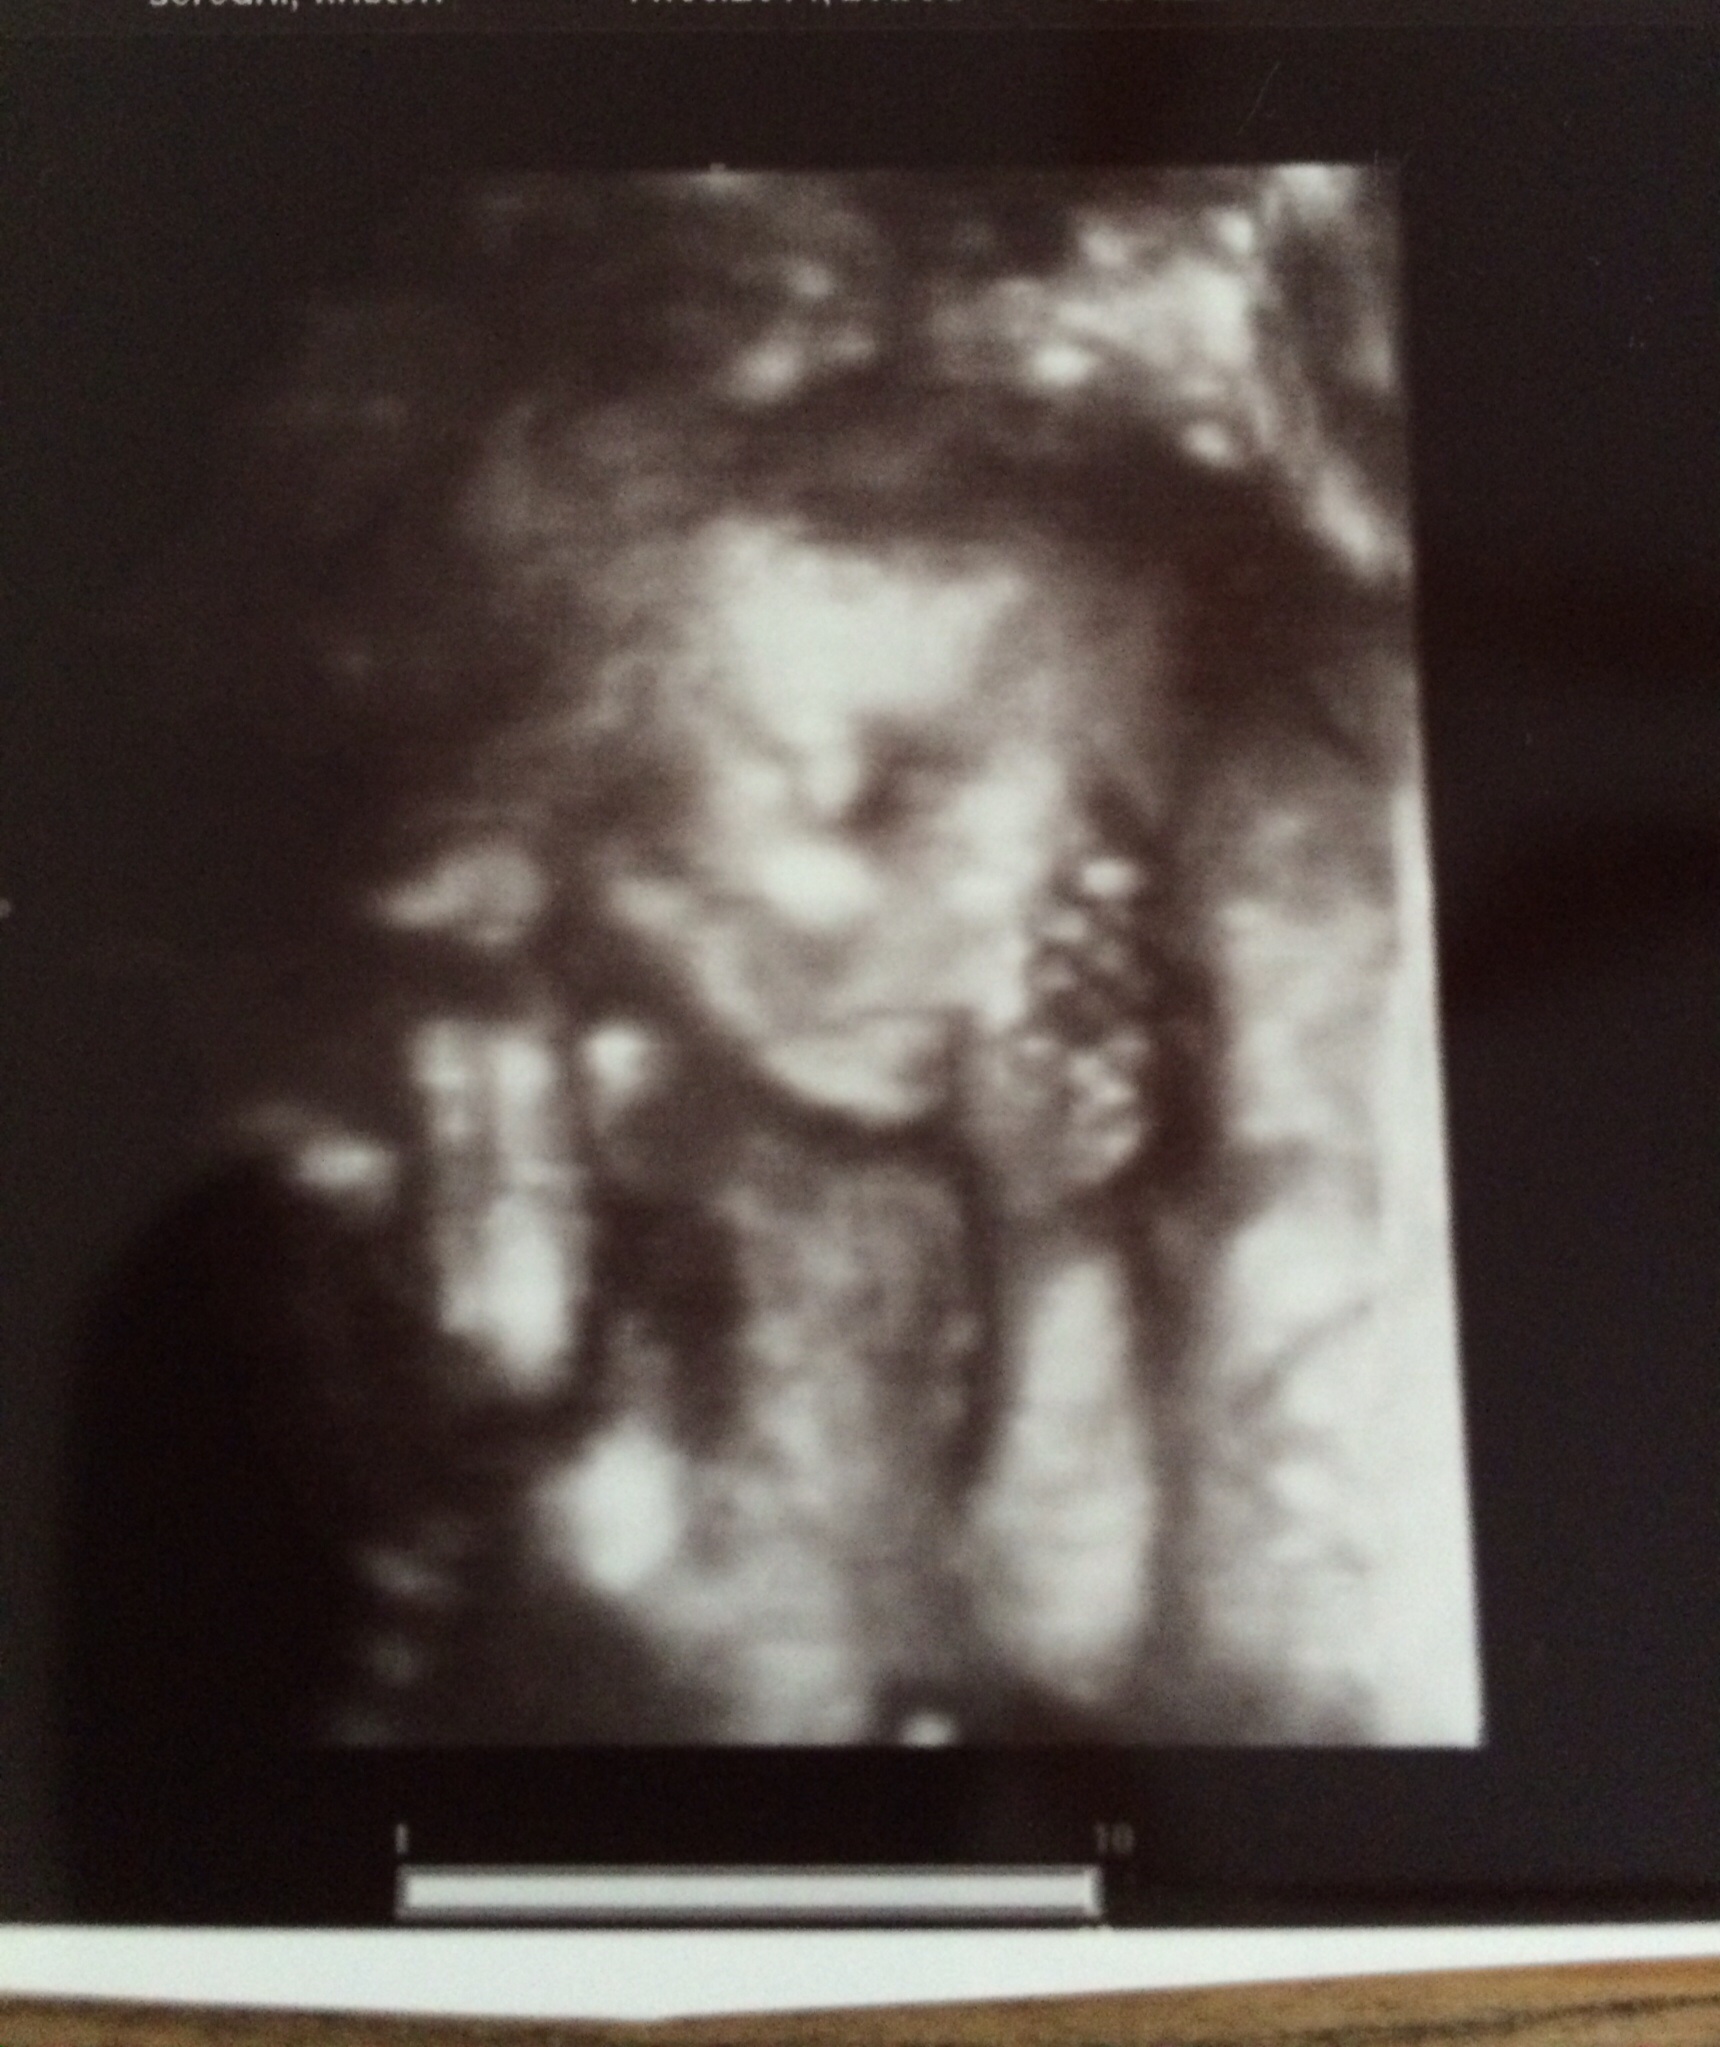

Had my 20w check up yesterday and baby Max was showing us all his tricks! We got good pictures of him touching his toes to his head and sucking his thumb. Still can't believe that's all going on in my belly!!

Awesome pics! I love that one with his toes touching his head. My tech told me that LO was in that position too but we didn't get anywhere as clear a picture of that! It's cool to see! Congrats on a great scan!